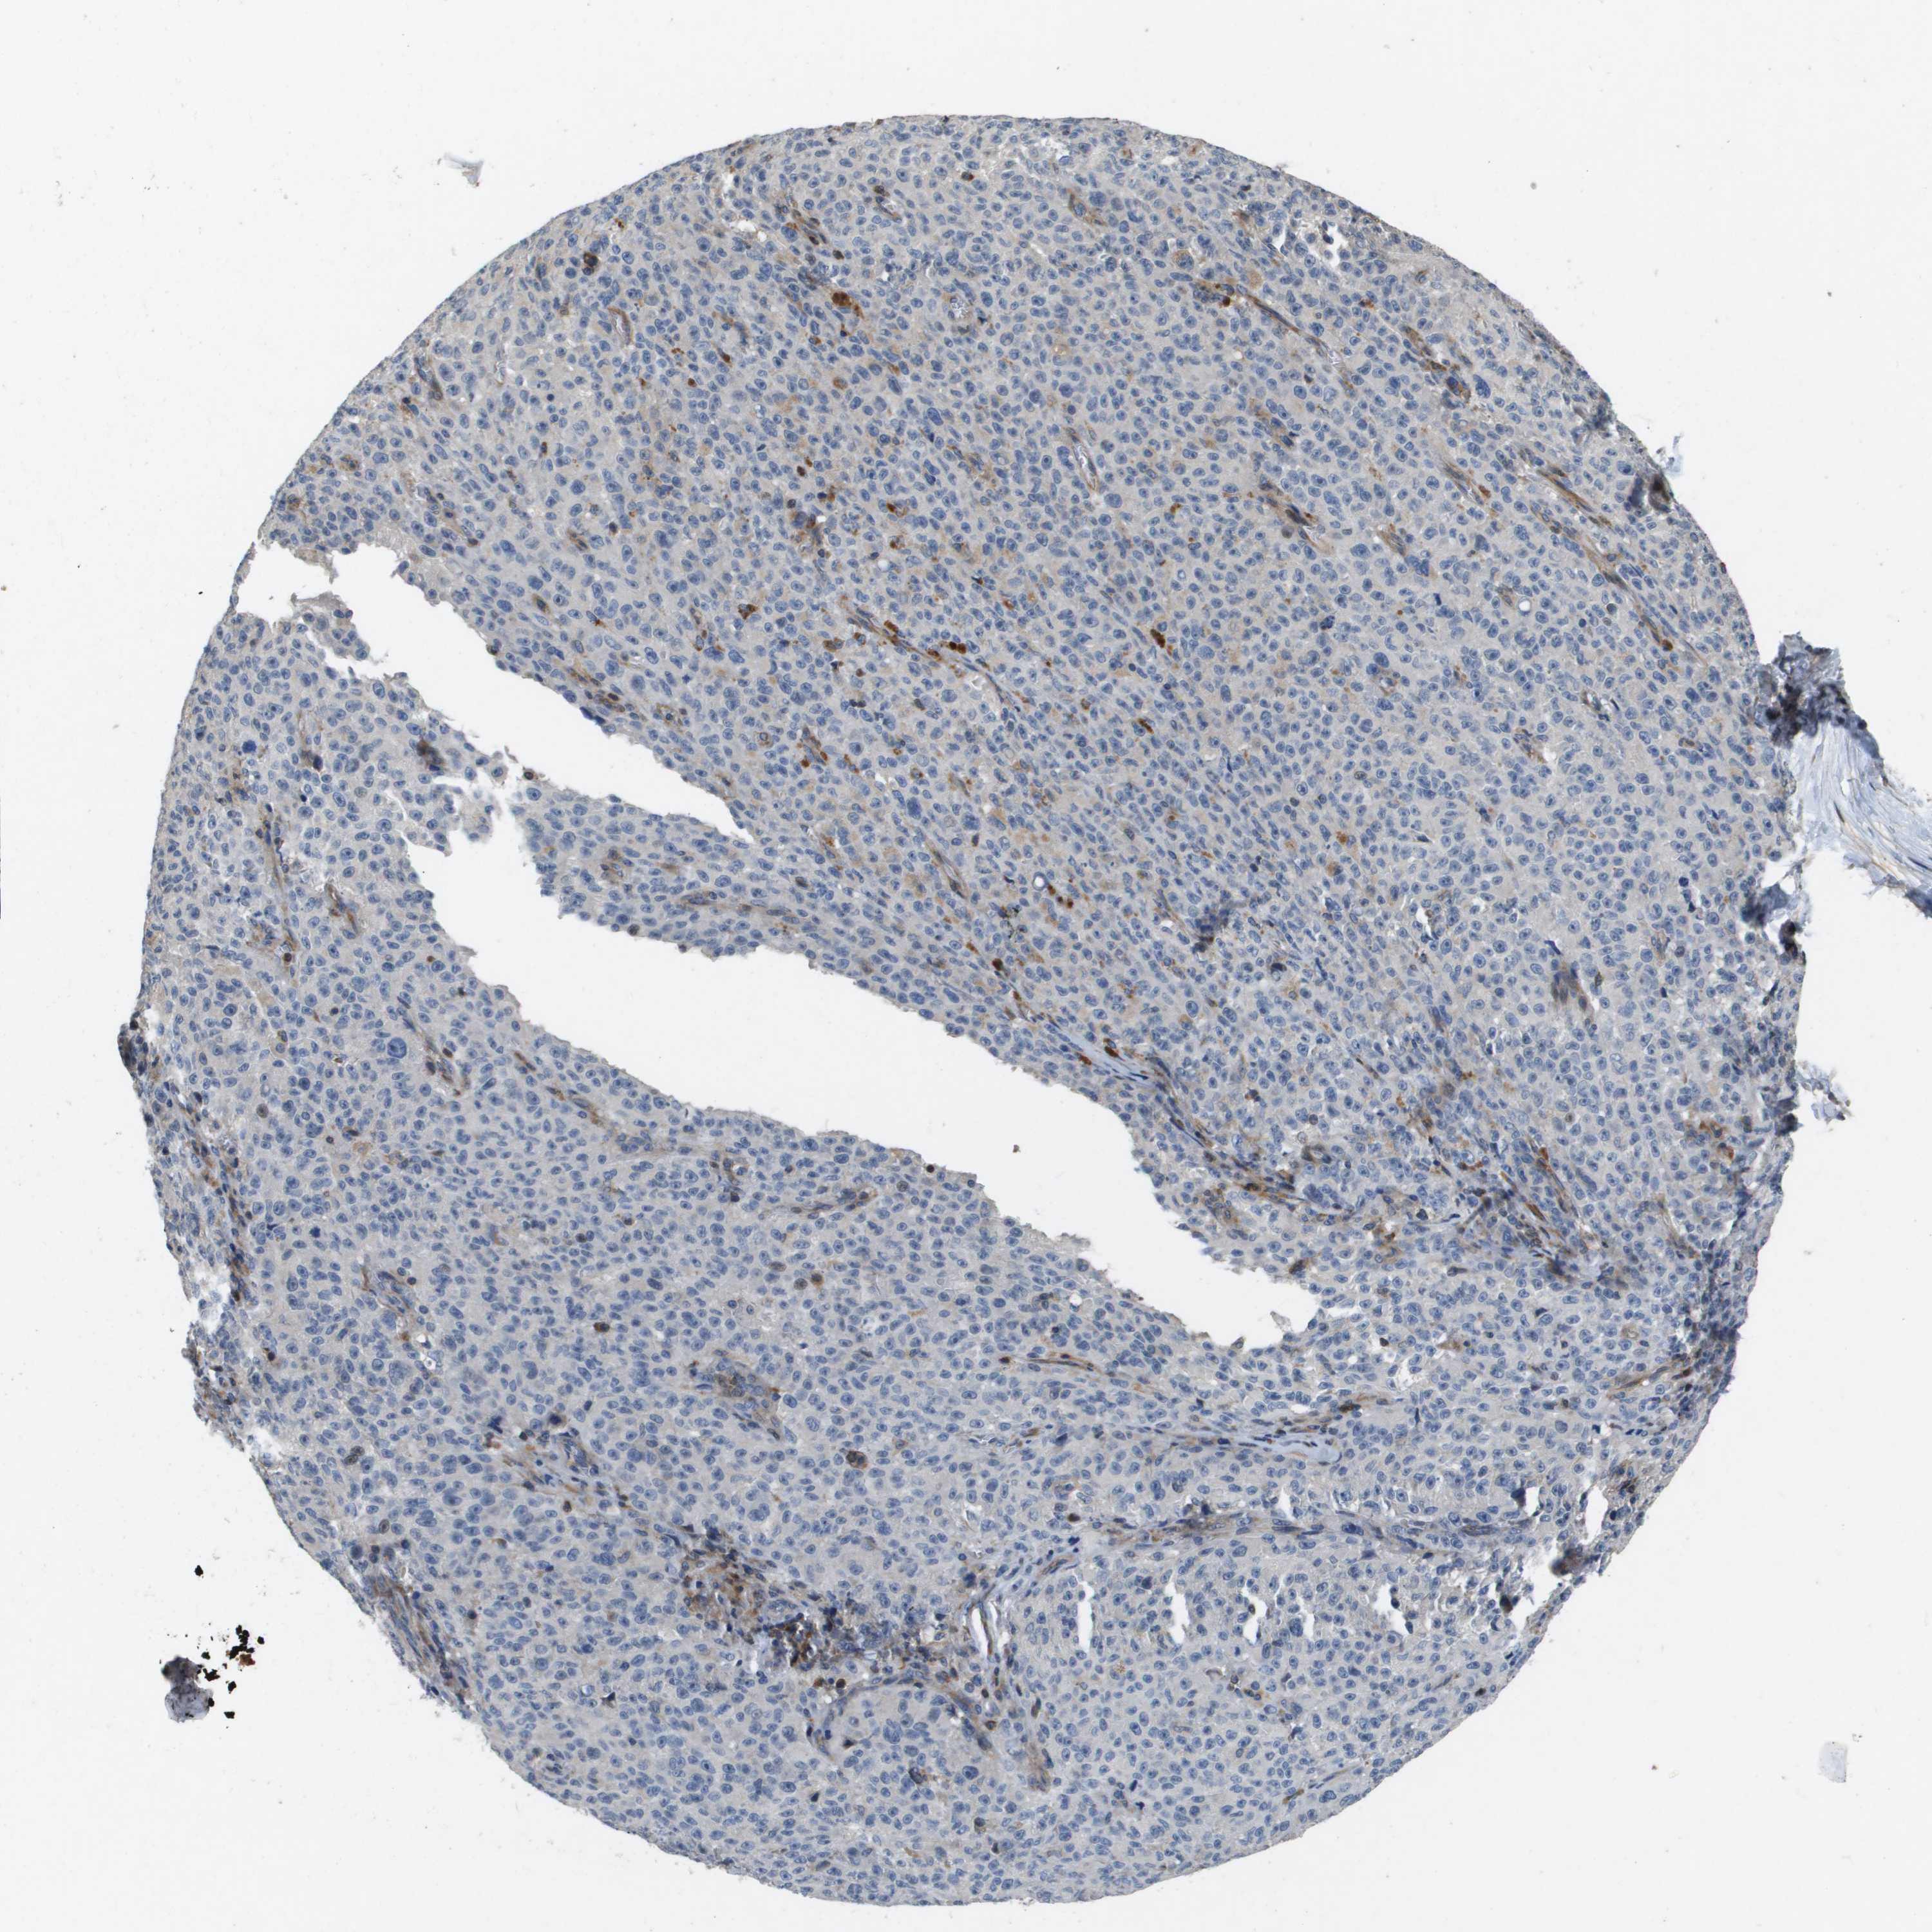

MELANOMA - Protein expressioni

A mouse-over function shows sample information and annotation data. Click on an image to view it in a full screen mode. Samples can be filtered based on level of antibody staining by selecting one or several of the following categories: high, medium, low and not detected. The assay and annotation is described here.

Note that samples used for immunohistochemistry by the Human Protein Atlas do not correspond to samples in the TCGA dataset.

Antibody stainingi

Antibody staining in the annotated cell types in the current human tissue is reported as not detected, low, medium, or high, based on conventional immunohistochemistry profiling in selected tissues. This score is based on the combination of the staining intensity and fraction of stained cells.

Each image is clickable and will lead to virtual microscopy that enables deeper exploration of all samples and also displays staining intensity scores, fraction scores and subcellular localization as well as patient and tissue information for each sample.

Antibody HPA017293

Staining

High

Medium

Low

Not detected

Intensity

Strong

Moderate

Weak

Negative

Quantity

>75%

75%-25%

<25%

None

Location

Nuclear

Cytoplasmic/membranous

Cytoplasmic/membranous,nuclear

Malignant melanoma, NOS

Malignant melanoma, Metastatic site